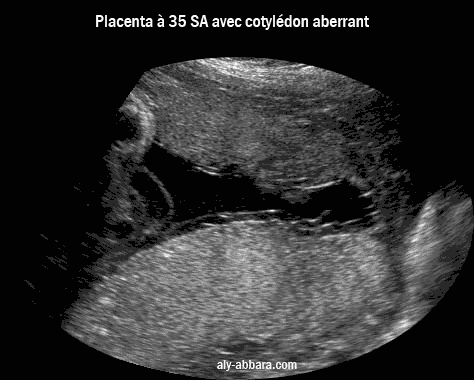

image échographique montrant un placenta à 35 SA avec un cotylédon aberrant ; on individualise au Doppler, Dynamic Flow, les vaisseaux sanguins reliant le cotylédon au placenta

Placenta d'une grossesse à 35 semaines d'aménorrhée un cotylédon aberrant ; on individualise au Doppler,

Dynamic Flow, les vaisseaux sanguin reliant le cotylédon au placenta.